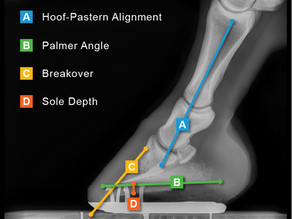

Keeping your horse sound over the long haul takes teamwork, especially between your farrier and your veterinarian. Consulting with the benefit of farrier films is one of the most effective ways we can work together to support your horse’s performance, comfort, and longevity.